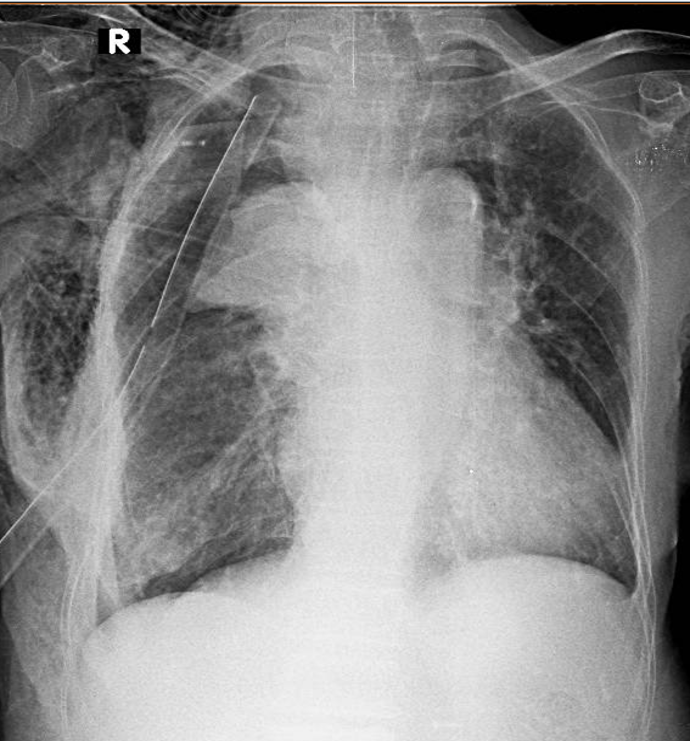

1-Viêm phổi mô kẻ thùy dưới (P) 2-Tràn khí màng phổi (P) đang dẩn lưu + xẹp thùy trên phổi (P) 3-Tràn khí dưới da thành ngực và vùng cổ (P) 4-Sonde dẩn lưu màng phổi (P) 5-Cung động mạch chủ đóng vôi